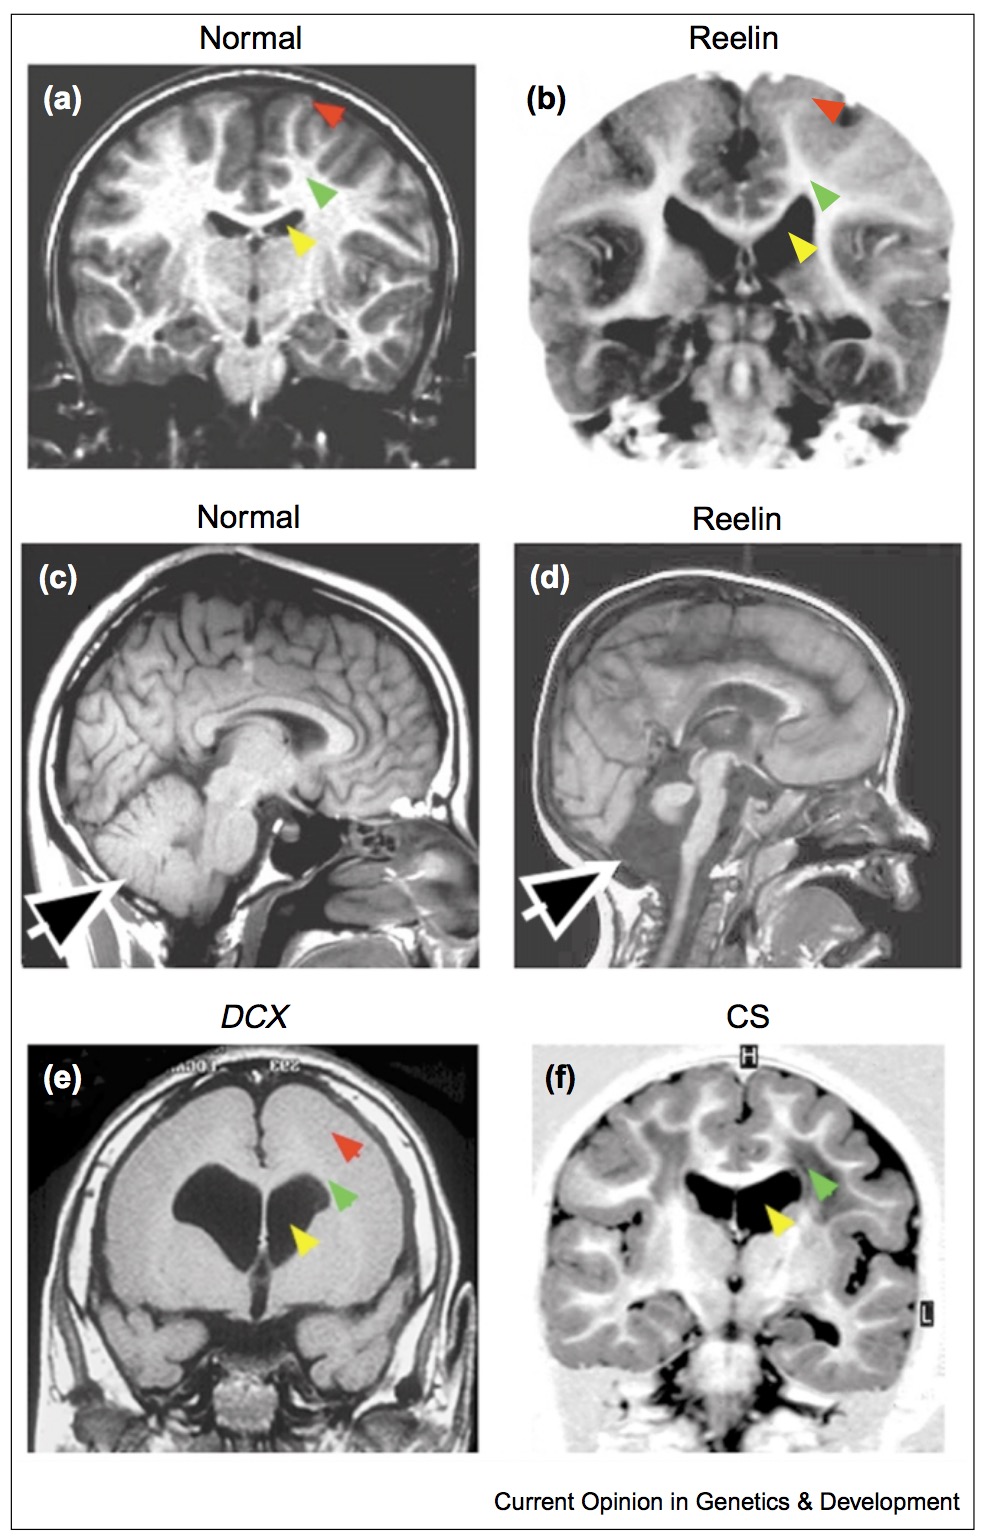

Defects in cortical development

- lissencephaly: smooth brain

- do not have characteristic gyri patterns

- leads to death, severe epilepsies and mental retardation

- cause is defects in neural migration during development